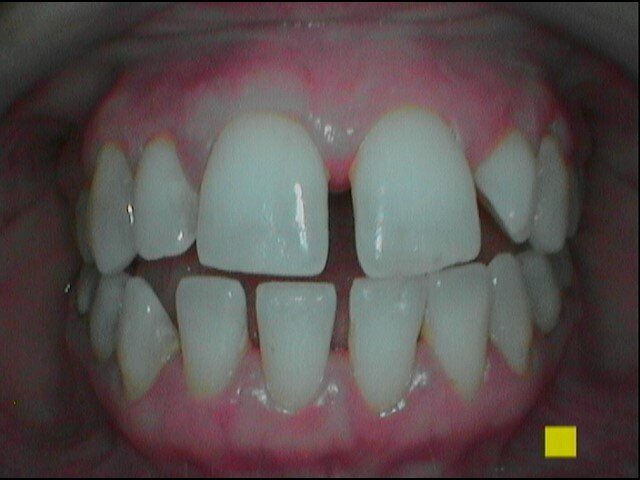

Per il mantenimento del sorriso luminoso, abbiamo consigliato di implementare la seduta di igiene con uno sbiancamento a base di aloe vera (moro white smile). Al controllo il paziente riferisce assenza di percezione di odori sgradevoli nel cavo orale e sul dispositivo invisibile con sensazione di freschezza dopo l’utilizzo del collutorio e di aver spazzolato e igienizzato la mascherina ortodontica con frequenza .Gli indici clinici sono PI pari al 10%, BoP negativo, PDD medio fisiologico (Figg. 14-16).